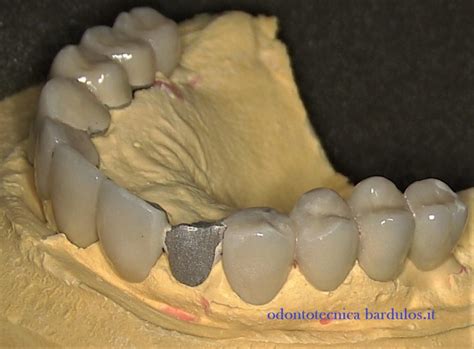

- Ceramica fratturata con esposizione dell'armatura metallica: Comune nelle protesi in metallo-ceramica.

- Ceramica fratturata con esposizione dell'armatura in ceramica: Osservata nelle protesi in ceramica integrale a doppio strato.